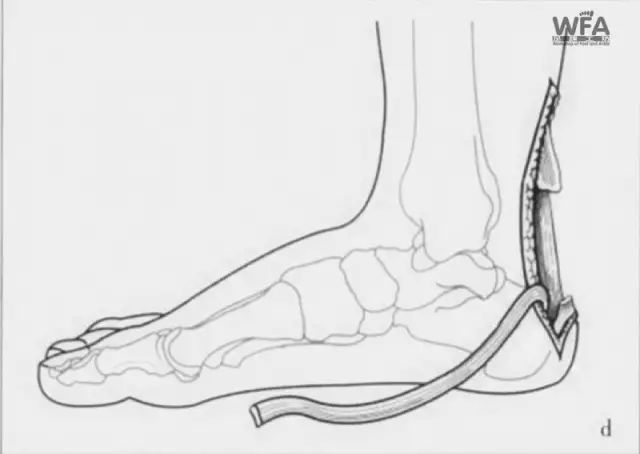

为了尽量规避以上问题,骨伤中心副主任许锦涛决定采用目前较有优势的微创切取全长踇(拇)长屈肌腱重建陈旧性跟腱断裂术。

术中,医护团队精细操作,“用脚底的肌腱修复脚后跟肌腱”,即用踇(拇)长屈肌腱修补跟腱,稳定踝关节。患者术后功能康复后良好,手术圆满成功。

微创切取全长踇(拇)长屈肌腱重建陈旧性跟腱断裂术的优缺点

本术式具有术后恢复快、肌腱固定强度高、并发症少的优势,不仅适用于慢性跟腱断裂缺损较大的患者,还适用于因慢性跟腱广泛病变,而需切除较大范围病变跟腱的患者,但不适用于对踇(拇)趾有较高要求的职业运动员和运动爱好者。

手术示意图

其中微创切取全长踇(拇)长屈肌腱重建陈旧性跟腱断裂术使用的踇(拇)长屈肌腱具有肌腱长、韧性好、肌力强、收缩力轴与跟腱类似等优点,有利于保持踝关节肌力平衡,常切取后用来修复跟腱、腓骨肌腱、胫后肌腱,手术具有安全可靠、疗效确切等优点,广受患者好评!